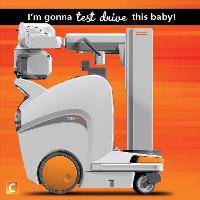

На рабочем месте производится обучение работе на Вашем оборудовании.

Любого доктора можно быстро подготовить как рентгенлаборанта и дать необходимые знания для оценки рентгенограмм.

Изучение проблемы низкого качества рентгенограмм на Вашем оборудовании.

Мобильный рентгенаппарат + оцифровщик. Получение рентгеновского изображения на экране ноутбука. Вариант за 1,4 миллиона рублей под ключ.

Мобильный рентгенаппарат с печатью рентгенограмм на рентгеновской пленке. Цена 700000 рублей.